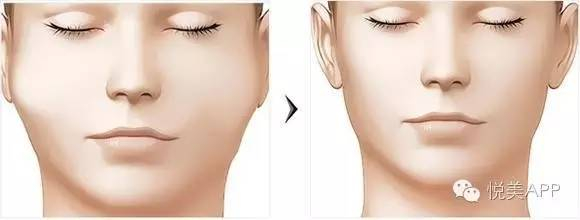

最让你自卑的是脸上哪个部位?眼睛?双眼皮手术几千块钱。鼻子?硅胶隆鼻也就几千。皮肤?那就皮肤管理啊~脸大?先减减肥,要是像大幂幂、熊黛林一样,长了嫩牛五方的骨骼↓

最后呈现颧骨降低,正面脸变窄的效果

颧骨手术是个魔术,把人变成4000年美女

把人瞬间变年轻

大饼脸变巴掌脸